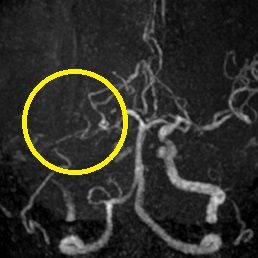

ろれつ困難と左半身重度麻痺のため当院に救急搬送となった患者様に対し、発症2時間30分でt-PAの投与を開始。t-PA開始1時間半後に左麻痺とろれつ困難は回復し始め、翌日には症状は消失。t-PA後のMRA検査で閉塞血管の完全再開通を認め、発症から2週間後に神経症状なく退院。

右大脳動脈閉塞(来院時MRA検査画像)

t-PA静注後